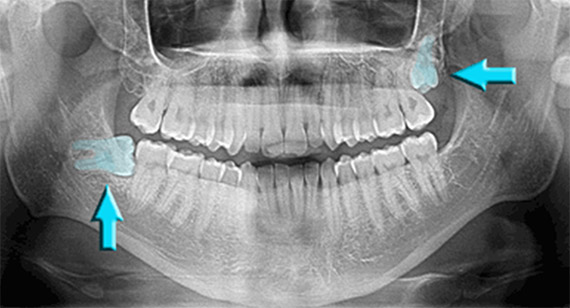

Impacted Wisdom Teeth (OPG) | Image | Radiopaedia.org

radiopaedia.orgImpacted Wisdom Teeth - City Dental Clinic

radiopaedia.orgImpacted Wisdom Teeth - City Dental Clinic

www.citydentalclinic.vnwisdom teeth impacted panoramic giudizio estrazione denti indicating sides

www.citydentalclinic.vnwisdom teeth impacted panoramic giudizio estrazione denti indicating sides

An X-ray Showing Impacted Teeth Growing Irregularly On Both Ends Of The